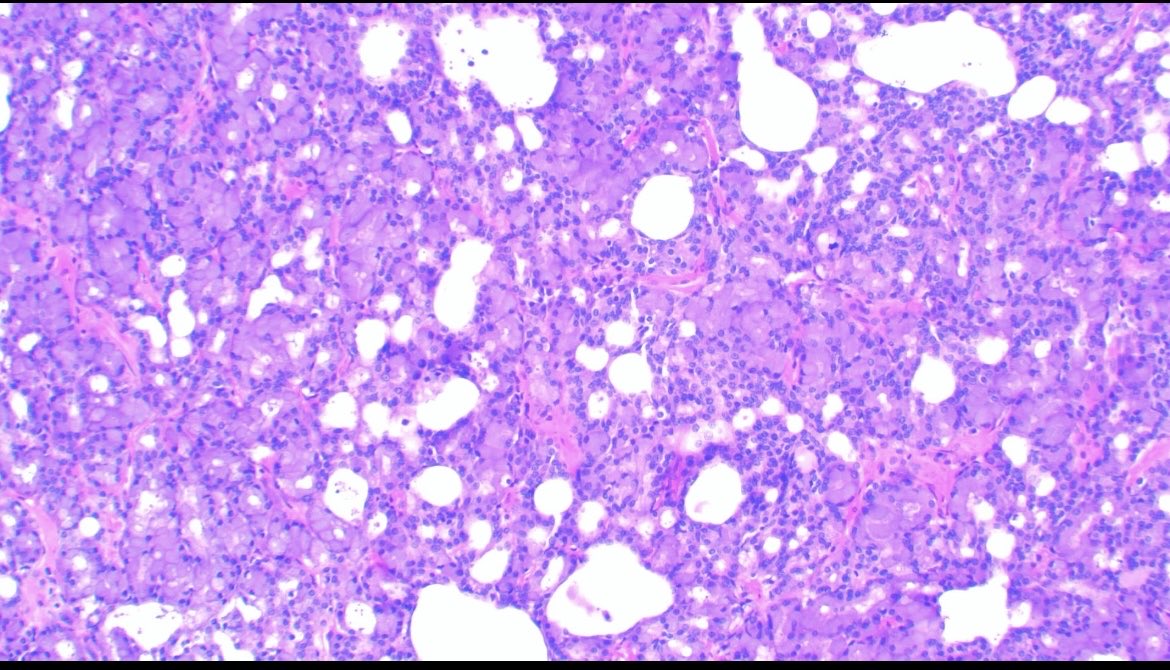

Uterine carcinosarcoma showing serous epithelial carcinoma and liposarcomatous heterologous element 🧐🧐 #Gynecology #WomensHealth #medicine #path #pathology